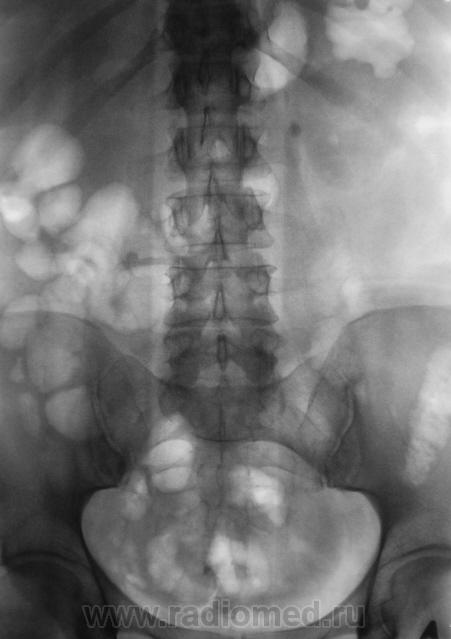

Ночь сплю не очень хорошо...мучают сомнения...с утра вызываю мужичка вновь...делаю контрольные прицельные снимки...

И вот он "красавец" - оказывается - он как маятник ходит из нижней чашки в лоханку, периодически вызывая нечетко выраженную колику, зато с микро- и макрогематурией....

Анализ - ноги ошибки "выросли" еще их первой обзорной урограммы, выполненной, мягко говоря, не совсем корректно....

Вот такая история...если она была кому то интересной и поучительной...